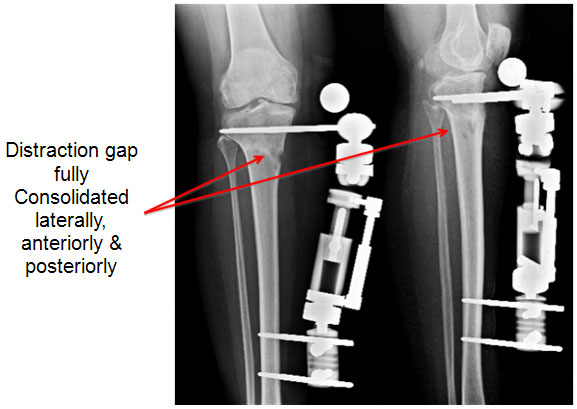

| 12 weeks post surgery – just before fixator removal |

| 12 weeks post surgery the distraction gap is consolidated well and osteotomy is healed. Even though a slight gap is seen on the medial cortex (inner border on the left picture), other 3 sides have healed well and patient is walking comfortably bearing full weight. |